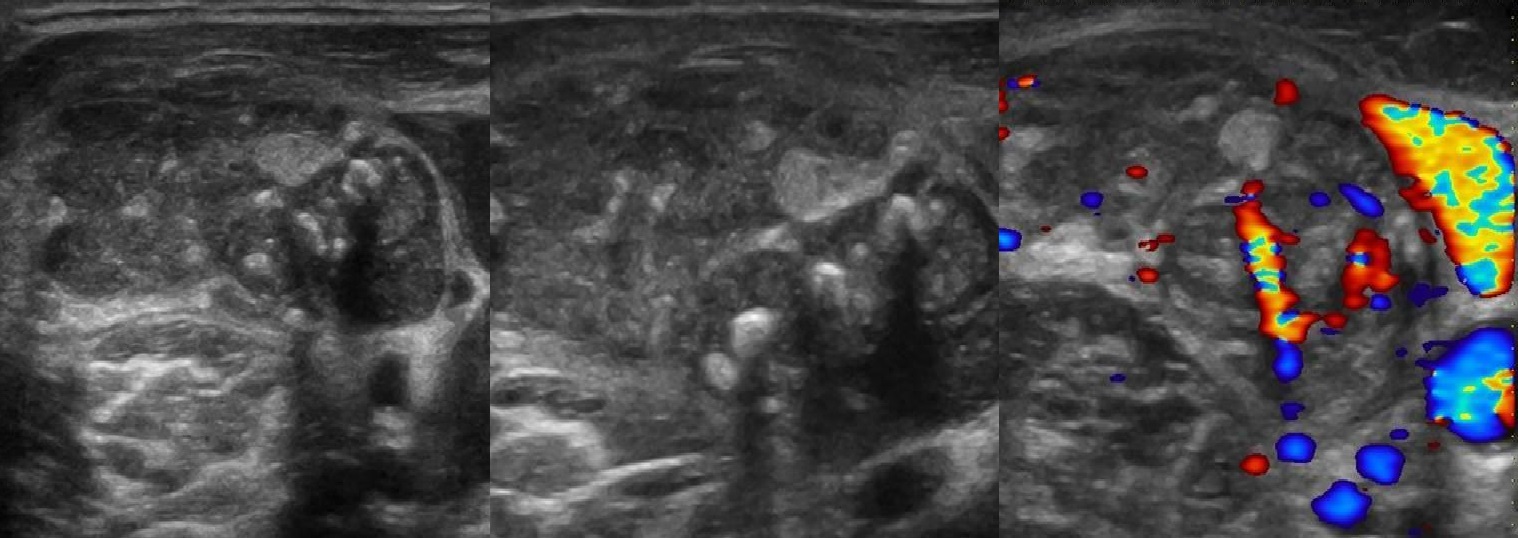

УЗИ лимфоузлов при лимфоме Ходжкина

Раздел: Образы вокруг